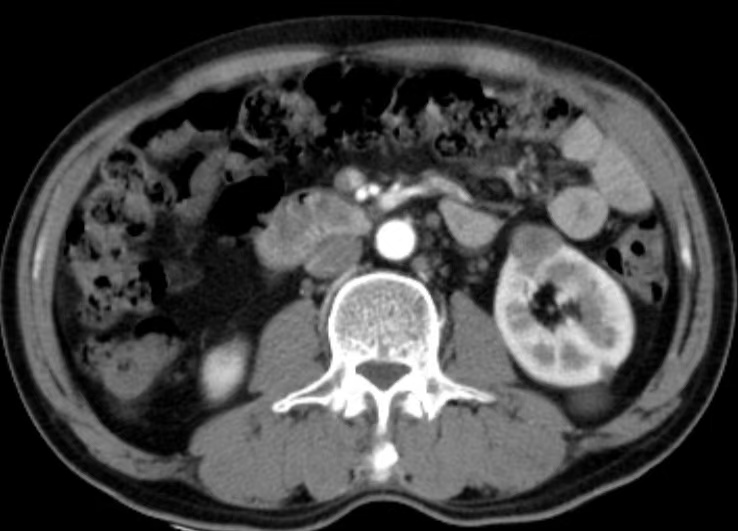

患者是一名60多岁男性,因“CT发现左肾占位”入院,完善泌尿系增强CT示“左肾肿瘤,考虑恶性可能”。

腹部增强CT

随后,我院泌尿外科迅速组织科室团队进行病情讨论及多学科专家会诊,在贵州医科大学附属医院泌尿外科专家的指导下,对病情、身体状况等关键因素进行全面、细致的评估,患者手术指征明确,医疗团队决定采用具有创伤小、恢复快、术后并发症少等优势的腹腔镜下肾部分切除术。